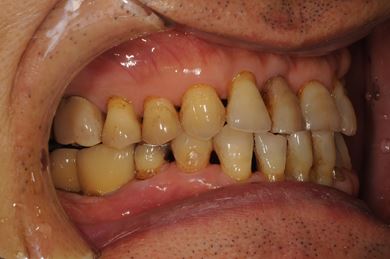

抜歯即日スピードインプラント治療+セラミック治療+歯肉遊離移植術

| 性別/年齢 | 男性 / 64歳 | ||||||||||||||||||||||||||||||||

| 主訴 | 左最奥の下部ブリッジが不安定になっており、奥2本のインプラントを考えたい。 | ||||||||||||||||||||||||||||||||

| 治療内容 | インプラント4本(抜歯即日スピードインプラント)、メタルボンドセラミッククラウン5本、ハイブリッドセラミッククラウン1本(ハイブリッドセラミック用土台1本) | ||||||||||||||||||||||||||||||||